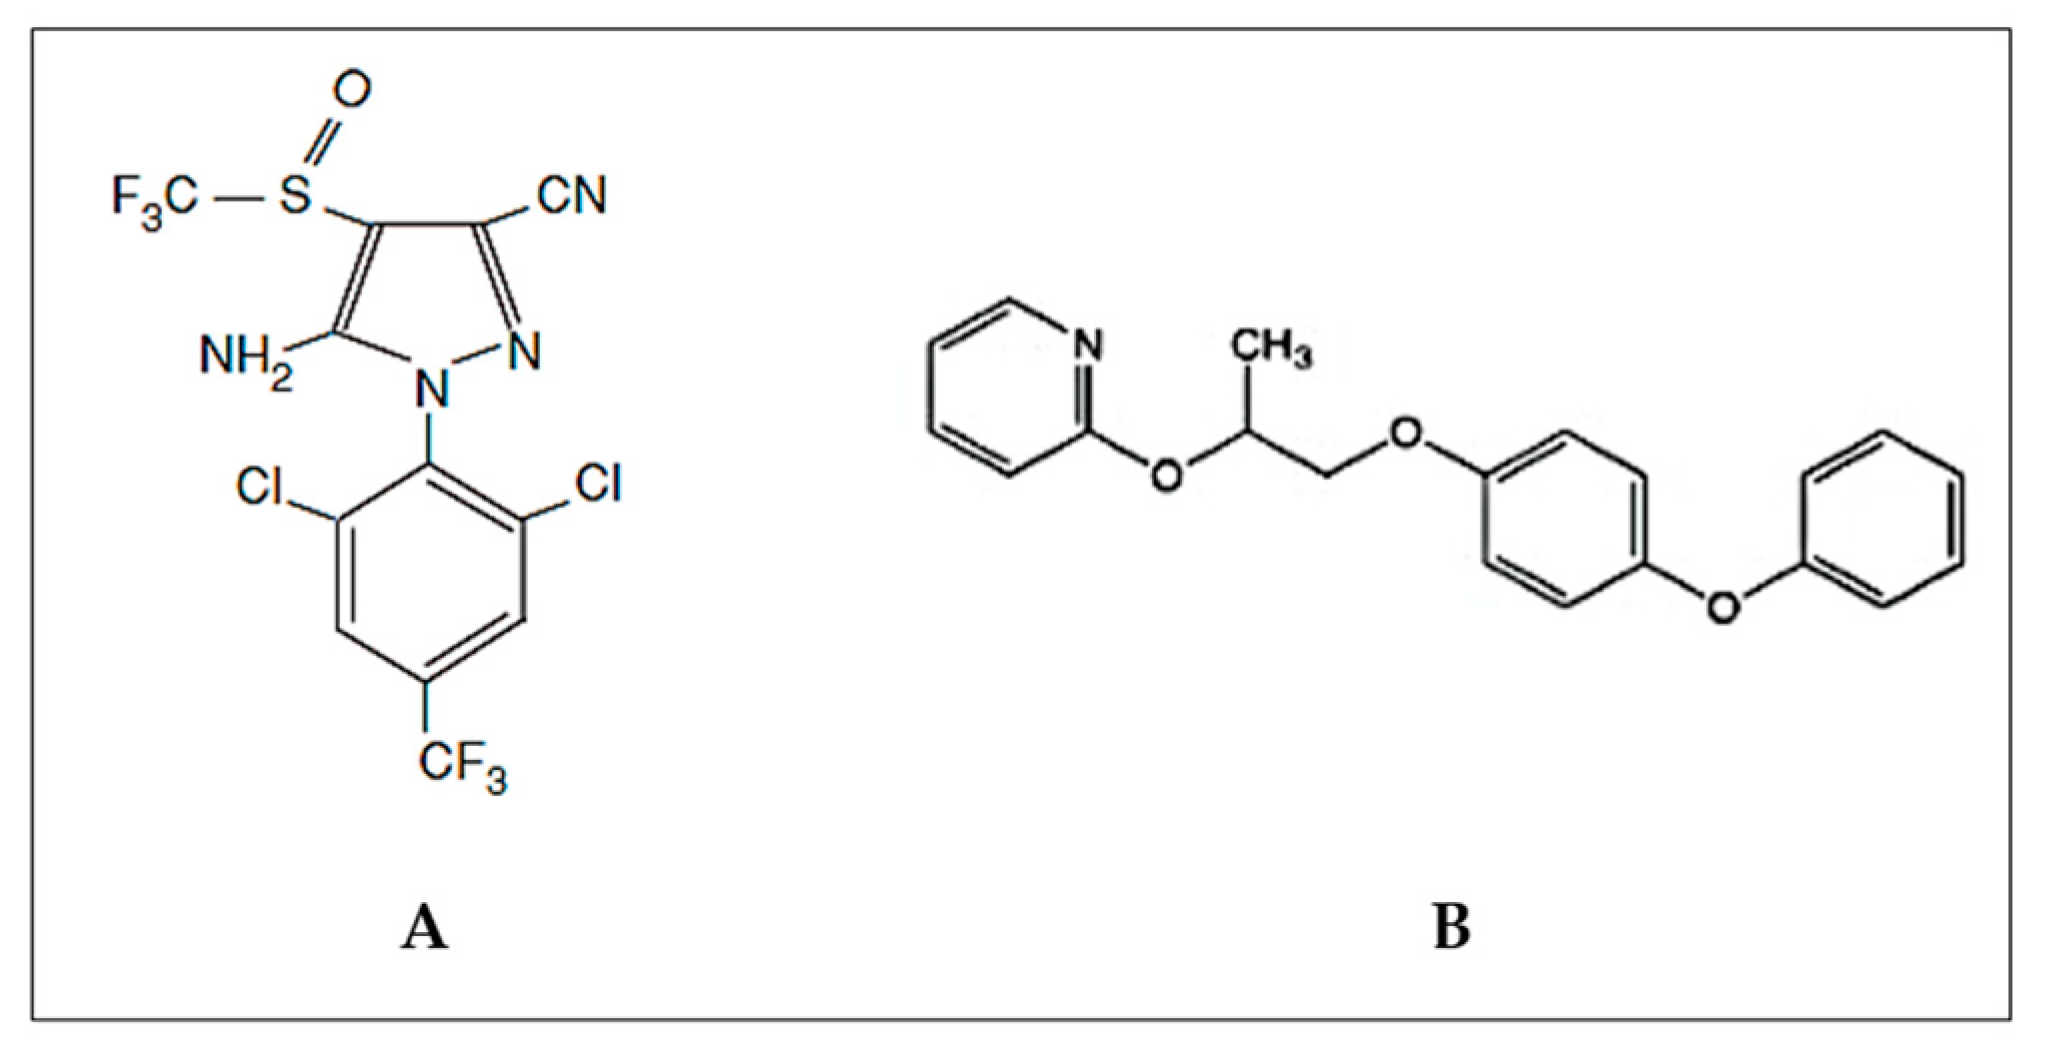

2.2. Chemicals

- Fent, G.M. Fipronil, 3rd, ed.; Wexler, P.B.T.-E., Ed.; Academic Press: Oxford, UK, 2014; pp. 596–597. ISBN 978-0-12-386455-0. [Google Scholar]

- Ishaaya, I.; Horowitz, A.R. Pyriproxyfen, a novel insect growth regulator for controlling whiteflies: Mechanisms and resistance management. Pestic. Sci. 1995, 43, 227–232. [Google Scholar]